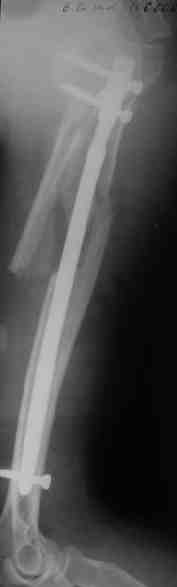

Прооперировали больную с переломом плеча все же гвоздем, Фото в приложении.

Отправитель: Никита Заднепровский 20 Август 2006, 22:38

Интересно, а канал рассверливали?

Гвоздик похоже ЦИТОвский?

Полагаю, бабушку можно поздравить с обретением

независимости. Судя по снимкам, неврологических расстройств нет и такая пациентка выпишется после снятия швов.

Немножко уточню ответы Максима.

Только сформировали канал в головке. Диафиз не рассверливали. Хотя при необходимости, конечно, рассверлили бы.

НЗ> Гвоздик похоже ЦИТОвский?

Гвоздь большеберцовый нашей модификации, действительно, их делает предпричятие "ЦИТО". Тут взят 9 мм, укорочен до 240 мм, сделано дополнительное отверстие самое проксимальное, ну и для дистального винта.

НЗ> независимости. Судя по снимкам, неврологических расстройств

НЗ> нет и такая пациентка выпишется после снятия швов.

Неврологии нет, а выписать можно хоть на второй день, швы можно снять и в местной больнице.

НЗ> Какие рекомендации Вы дадите этой женщине на ближайшие 6 месяцев?

Почему так надолго? На ближэайшие недели - разработка движений, и все. Полагаю, что недель после 4 никаких рекомендаций не будет нужно, просто жить обычной жизнью сельской пенсионерки.